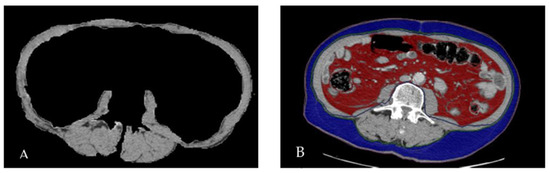

2.3. Body Composition Analysis